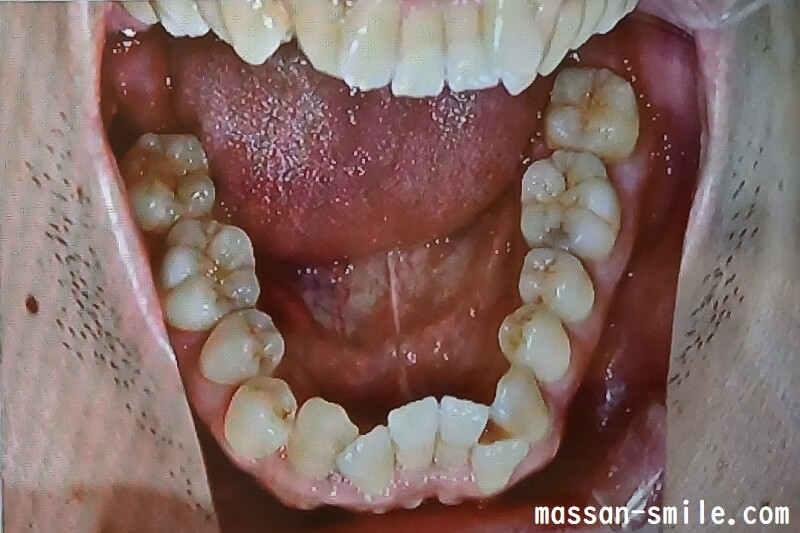

画像を見てもらえれば(↓)と思いますが、私の場合、もともと上の前歯が1本足りないです。

下の前歯は、本数は正常ですが、入りきらなくてガタガタになっています。

- 歯列矯正前の歯並び

そしてその状態から、前歯上下の歯並びを整えていくという方法でした。